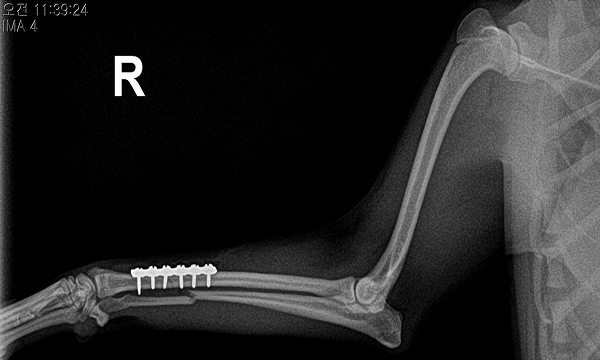

수술케이스 ① 몽*강아지 - 중수골 다발골절

수술케이스 1 before BEFORE

수술케이스 1 after AFTER